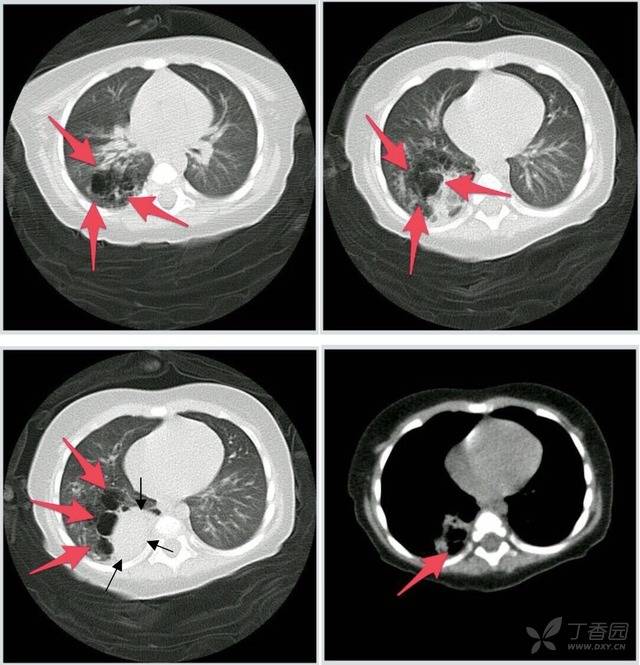

胸片(图1)发现左下叶肺泡处阴影,ct(图2)同样可见,另外还发现右下叶